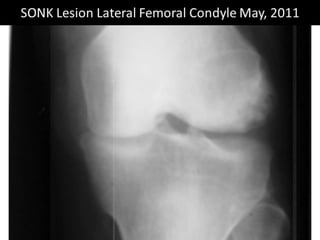

The document presents a detailed case study of a patient with transient osteoporosis of the hip (TOH) and spontaneous osteonecrosis of the knee (SONK) treated at Choithram Hospital & Research Centre in India. Over 20 years, the patient experienced multiple episodes of TOH and SONK with no history of trauma or co-morbidities, resulting in resolutions and recurrences of conditions. The information is intended for orthopedic surgery students and highlights personal experiences and case collections, with a disclaimer regarding content usage and potential controversies.